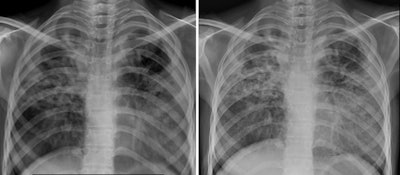

Chest x-ray images for the same individual with evidence of tuberculosis using (A) the Mine 2 machine, and (B) a standard digital x-ray machine. Image courtesy of the Indian Journal of Medical Research through CC BY 4.0.According to the findings, the intraobserver (radiologist) agreements regarding the status of 15 chest x-ray parameters between the images ranged between 74% and 100%, with an unweighted mean of 87.2%, the group reported. In addition, in an overall comparison of image quality (on a scale of one to 10, with 10 denoting highest quality), the handheld x-ray images had a score of 9 and the digital chest x-ray images had a score of 8, the researchers stated.

"The current study shows that a handheld x-ray machine, which is easy to use and can potentially be carried to any area, produces x-ray images with quality that is comparable to digital x-ray machines routinely used," the group wrote.